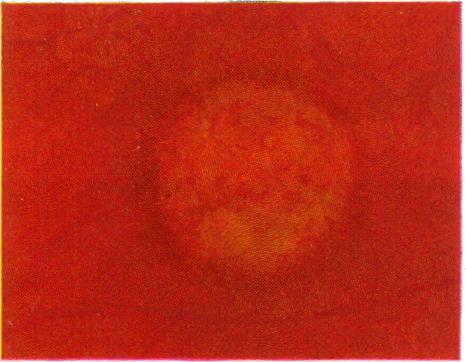

Braley A E, Spivey B E

Trans Am Ophthalmol Soc. 1963;61:339-71.